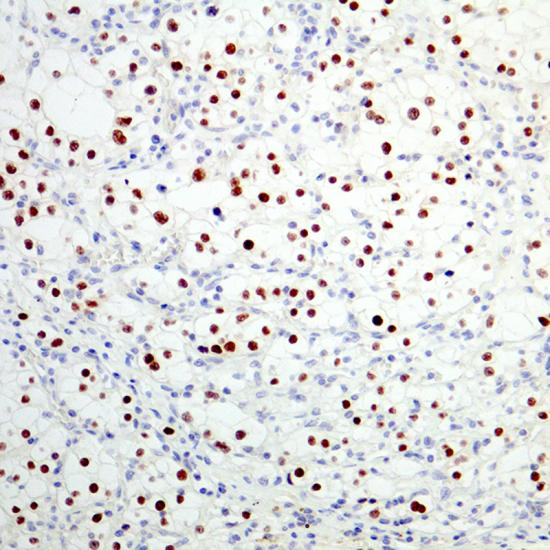

Pax-2

Pax-2抗體試劑(免疫組織化學(xué)) 閩廈械備20180284號(hào)

細(xì)胞核

腎細(xì)胞癌

Pax-2基因是Pax家族9個(gè)成員之一,是唯一可在腎臟表達(dá),又和腎臟形態(tài)發(fā)生密切相關(guān)的基因,主要參與早期腎臟足細(xì)

胞、腎小管上皮細(xì)胞分化的調(diào)控,對(duì)以后的內(nèi)皮細(xì)胞、系膜細(xì)胞的發(fā)育亦有引導(dǎo)作用。Pax-2是低級(jí)別的腎透明細(xì)胞癌的有用標(biāo)記物,研究表明在低級(jí)別的腎透明細(xì)胞癌中Pax-2表達(dá);而在高級(jí)別的腎透明細(xì)胞癌中,Pax-2 的表達(dá)降低或缺失。Pax-2 在絕大多數(shù)的腎乳頭狀細(xì)胞癌、嫌色細(xì)胞癌和嗜酸細(xì)胞瘤中不表達(dá)。